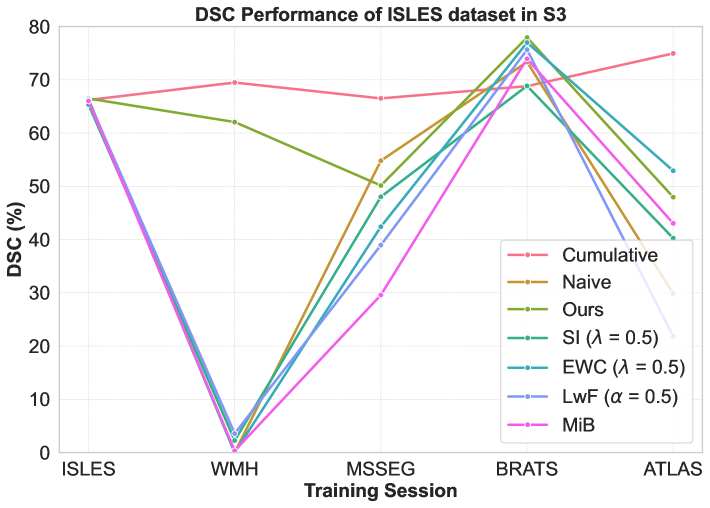

We compare the proposed strategy against popular CL strategies, including EWC [Kirkpatrick et al.(2017)Kirkpatrick, Pascanu, Rabinowitz, Veness, Desjardins, Rusu, Milan, Quan, Ramalho, Grabska-Barwinska, et al.], SI [Zenke et al.(2017)Zenke, Poole, and Ganguli], LwF [Li and Hoiem(2018)], MiB [Cermelli et al.(2020)Cermelli, Mancini, Bulo, Ricci, and Caputo], Replay [Rolnick et al.(2019)Rolnick, Ahuja, Schwarz, Lillicrap, and Wayne], and GDumb [Prabhu et al.(2020)Prabhu, Torr, and Dokania] in 3D-UNet. To establish baselines, we report lower bound performance with naive, and upper bounds with cumulative and joint training. Naive corresponds to traditional fine-tuning on new datasets, joint training uses all datasets simultaneously, and cumulative training sequentially incorporates all previous data. Experiments were conducted using Avalanche 0.6.0 framework [Lomonaco et al.(2021)Lomonaco, Pellegrini, Cossu, Carta, Graffieti, Hayes, Lange, Masana, Pomponi, van de Ven, Mundt, She, Cooper, Forest, Belouadah, Calderara, Parisi, Cuzzolin, Tolias, Scardapane, Antiga, Amhad, Popescu, Kanan, van de Weijer, Tuytelaars, Bacciu, and Maltoni]. The buffer size was set to for Replay and GDumb. Regularization factors ( in LwF and in SI and EWC) were tuned within 0.5, 1.0, 1.5, 2.0, and was fixed at . For our method, we set , , and . For domain-conditioned MoE, we consider maximum modalities as (PD, FLAIR, T1, T1c, T2, DWI) and pathology as (Tumor, Stroke lesion, Sclerosis lesions, White matter hyperintensity). An example of the binary domain-conditioned token () for a sample with FLAIR and T1 modality and “stroke lesion” pathology would be [0, 1, 1, 0, 0, 0, 0, 1, 0, 0]. We tested on four dataset sequences: S1 (high to low dataset size: {BRATS, ATLAS, MSSEG, ISLES, WMH}), S2 (descending modality count: {MSSEG, BRATS, ISLES, WMH, ATLAS}), S3 (low to high dataset size: {ISLES, WMH, MSSEG, BRATS, ATLAS}), and S4 (ascending modality count: {ATLAS, WMH, ISLES, BRATS, MSSEG}).

Performance comparison with others: For the considered medical applications, the primary concern will not be on improving zero-shot performance (FWT) but rather on minimizing forgetting (BWT) and enhancing the average DSC of the model (ACC and ILM). While FWT is reported for completeness, our analysis emphasize ACC, ILM, and BWT. Table 2 presents the ACC, ILM, BWT, and FWT values for all methods across sequences S1, S2, S3, and S4. Across all sequences, CL approaches (GDumb, Replay, MiB, LwF, SI, EWC, and the proposed method) mostly outperform naive training, highlighting the importance of mechanisms to mitigate catastrophic forgetting in UNet-based segmentation tasks. Further, as expected, approaches storing past data partially (Replay, GDumb) or fully (cumulative, joint training) show higher performance compared to methods (naive, MiB, LwF, SI, EWC, and the proposed approach) with no access to past exemplars. When comparing the proposed method to other buffer-free approaches (MiB, LwF, SI, EWC), it consistently achieves superior performance in all the sequences S1, S2, S3, and S4. Unlike these existing CL methods, which penalize large deviations from previously learned weights through response-level regularization terms in the training loss, the proposed approach introduces a drift-based dynamic penalization factor along with a latent-level regularization. This drift-based dual distillation allows for more effective mitigation of catastrophic forgetting. The proposed method shows a positive gain in (ACC, ILM, BWT) over best performance achieved among state-of-the art buffer-free approaches (blue colored in Table 2). Specifically, we observe an improvements of (25.51%, 9.23%, 34.34%) in S1, (6.57%, 25.28%, 31.85%) in S2, (4.85%, 11.02%, 40.15%) in S3, and (7.67%, 10.65%, 17.62%) in S4. For intuitive visualization, radar plots for S1, S2, S3, and S4, comparing cumulative, naive, the best-performing buffer-free methods, and the proposed approach are provided in Fig. 6 of Appendix.

Performance of a dataset in different sessions: We closely analyze CL model’s performances on first/second dataset upon learning other datasets in a given sequence. Specifically, Figure 3 shows DSC for BRATS in S1 and S2, ISLES in S3, and WMH in S4, with cumulative training included for reference. While cumulative training offers stable results, it requires access to all previous datasets, which is impractical in real-world scenarios. The naive approach shows significant DSC degradation, with high standard deviations of 33.91 (S1) and 40.23 (S2), 26.31 (S3), and 24.78 (S4) reflecting instability. In contrast, our CL strategy maintains stability, with much lower standard deviations of 5.19 (S1), 14.51 (S2), 11.37 (S3), and 15.50 (S4) highlighting its increased robustness against forgetting. Other buffer-free CL methods (MiB, SI, EWC, LwF) show better performance than naive training (Table 2) but still exhibit instability in DSC, with standard deviations of (28.80, 17.86, 31.14, 25.98) for S1, (36.75, 36.75, 35.85, 40.10) for S2, (25.43, 23.51, 25.65, 25.11) for S3, and (25.06, 15.51, 22.84, 23.55) for S4. While these methods perform well for natural images, their effectiveness is limited in brain MRI segmentation under domain shifts. In contrast, our approach delivers better stability and mitigates catastrophic forgetting effectively. Detailed segmentation visualizations for BRATS are provided in Appendix A.

Impact of dataset orders: We study the impact of different sequences on overall performance. We analyze ACC, ILM, BWT by best performing other CL methods and proposed approach for S1-S4 in Table 2 (summarized in Table 4, Appendix). We can see that best ACC is poor in S2 (28.54) and S3 (35.85) as compared to that in S1 (54.31) and S4 (50.67). Notably, all methods (except EWC) showed performance degradation when ATLAS (a single-modality dataset) was introduced later in sequences (S2, S3), adversely impacting the generalization of previously acquired knowledge in the model. This occurs because “modality dropping”, a critical generalization technique, cannot be applied to ATLAS due to its single-modality nature. Consequently, learning ATLAS in the later stages negatively impacts the model’s prior generalization capability. In contrast, when we learn datasets with fewer modalities at the start of sequences (S1 and S4), their negative effect is covered at later stages when we learn datasets with more modalities.